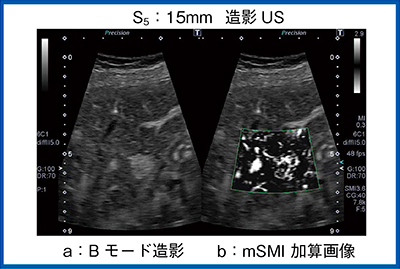

S5に15mmの結節を指摘された症例である。MRIでは指摘できず,Bモードではかすかに低エコーの領域が見られた。明瞭なハローもモザイクパターンもないが,ADFでは低エコー領域に入る血管が認められた。これに対してROIを絞ってSMI,SMI加算画像で確認すると,低エコー領域の中心から放射状に走る腫瘍血管が観察された。さらに,造影により明瞭な腫瘍濃染と血管構築が描出され,後血管相でも欠損像を認めないことよりFNHと診断した(図8)。

図8は門脈優位相から後血管相の間に観察したものだが,SMIはこのように明瞭な放射状の血管走行をボタン1つでいつでも加算画像で確認でき,簡単に評価することができる。

図8 限局性結節性過形成(FNH)